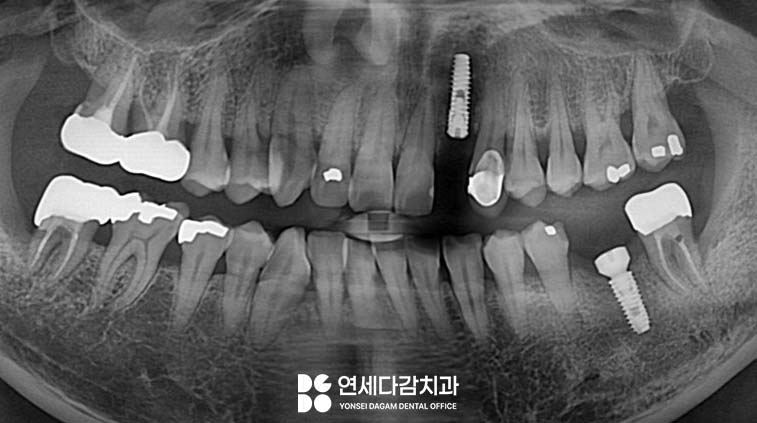

다행히 개롱역 치과 에서는

진료 후 정기적인 검진을 통해

치료된 부위가 잘 유지되고

있음을 확인했습니다.

그 결과 삶의 개선에 도움이 되었는지

반대쪽에 있던 치아 결손 부위도

임플란트를 진행 중에 있습니다.